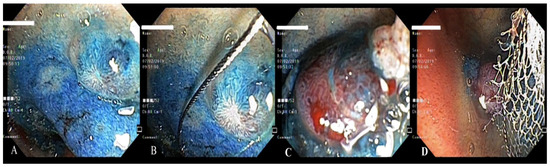

2. Case Report 1